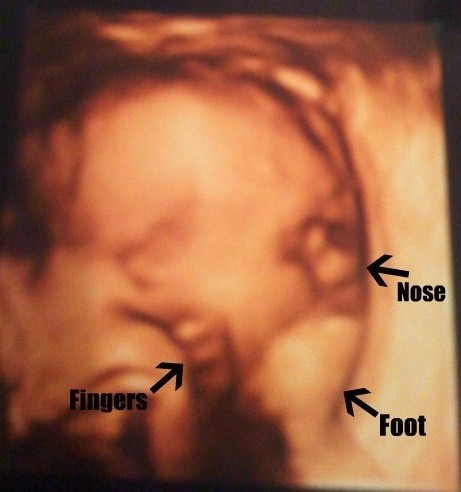

I know that everything that has recently happened in my life is not a coincidence. I think it happened for a reason. The day prior to finding out I was carrying conjoined twins who share one heart, the discussion topic at my church group was abortion. Then, the next day, my doctor told us there is no chance that they will live and that I should get an abortion. Right then I was faced with the big question should I keep them? This proved to be a huge test of my faith to either go through with a heartless abortion or to choose life for my children. I willingly and knowing chose life for my daughters Faith and Hope.